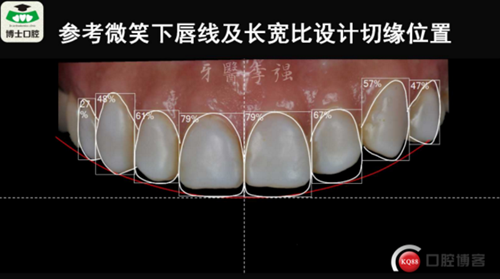

樹(shù)脂貼面與瓷貼面的孰是孰非~牙醫(yī)李強(qiáng)(濟(jì)南博士口腔)

樹(shù)脂貼面與瓷貼面的孰是孰非~牙醫(yī)李強(qiáng)(濟(jì)南博士口腔)

樹(shù)脂貼面與瓷貼面的孰是孰非~牙醫(yī)李強(qiáng)(濟(jì)南博士口腔)